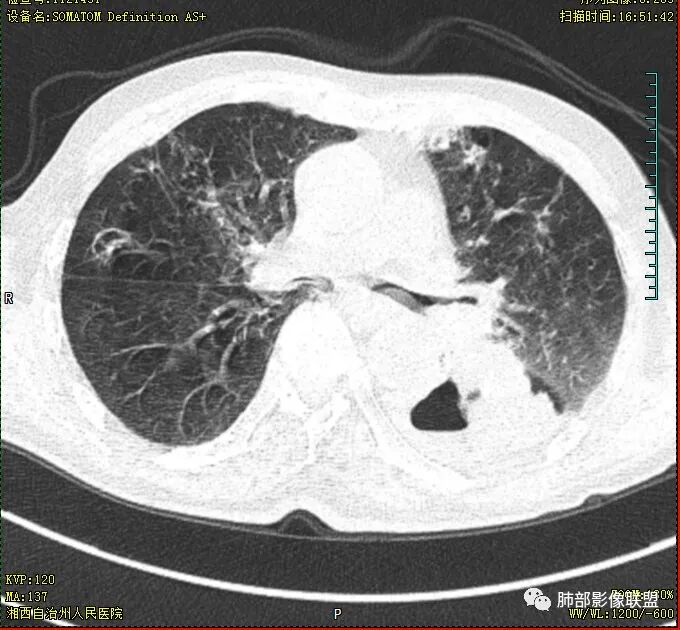

晨读 双肺多发斑片、斑点影,可见树芽征,支气管播散,右肺上叶小空洞,左肺下叶厚壁空洞,内壁较光整,有浅液平,右下叶背段支气管变窄,不均匀强化。结合临床考虑结核并感染,待排除合并肺癌可能。

晨读:老年男性患者,痰中带血伴间断发热2周,体温39.4℃,白细胞、中性粒细胞,CRP增高,Tspot阳性,胸部CT:双肺病变,左肺下叶背段大片实变密度影,边界模糊,内部见空洞形成,空洞内壁总体光滑,有气液平,增强扫描轻度不均匀强化,一月后复查空洞消失,实变影吸收减少,考虑感染性病变,结核伴肺脓肿。

晨读,老年男性,中等病程,咳嗽,痰中带血,发热,主病灶位于左肺下叶空洞,厚壁,偏心,内壁光滑,边界清楚,不均匀强化,内有坏死,考虑结核,内有气液平,周围部分小叶中心结界,好热,白细胞升高,合并感染。结核合并感染,鉴别肺癌合并感染。

老年慢性长期吸烟,痰中带血伴发高热。左下肺大片不均质实变里可见一含气液平厚壁空洞,内壁有坏死物残留,增强可空洞壁明显强化轮廓显示清晰,空洞位于肺门侧,近端支气管壁不规则增厚。两肺散在斑片状影,并见小树芽。18号复查肺窗空洞显示不清,20号用了俯卧位扫描,液体向下流动空洞又显示出来了。左下肺病灶有变小,还是考虑感染性病变,结核合并感染,鉴别鳞癌。

老年患者。左肺下叶厚壁空洞,有液平面。空洞内壁较为光整。病灶的内侧见支气管节段性的变窄扭曲。两肺内,弥漫性的广泛性的播散病灶。考虑感染性病变。肺结核并空洞形成两肺内播散。鉴别诊断-左肺下叶鳞癌。

双肺多发结节影,树芽征,小叶中心分布,左肺下叶不规则空洞,洞内壁光滑,见液平,洞壁似与支气管相通,增强扫描明显强化,可见血管造影征。三周左右复查空洞明显缩小。

双肺多发点片、索条斑条灶,见多发树丫征,左下肺大片不均质实变,内见一含气液平厚壁空洞,壁厚,内壁有坏死物残留,增强可空洞壁明显强化

,空洞位于肺门侧,近端支气管壁不规则增厚。

胸部CT:双肺多发小斑片、树芽、索条灶,左下肺大片不均质实变,远肺门侧厚壁空洞,气液平,内壁有坏死物残留,增强可空洞壁不均匀强化,近端支气管壁不规则增厚堵塞,实变影内可见与洞壁平行支气管。抗炎3周有缩小。

3.注意到左肺下叶空洞性病灶,腔壁厚度不均,环形强化较为明显,壁间支气管血管影走行,腔内液气平面,这通常见于感染性病灶,如脓肿,经治疗病灶吸收也高度支持病灶主体成分为脓肿。